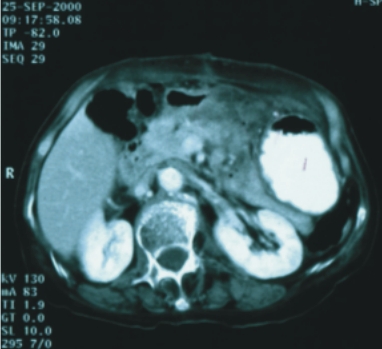

68歲/女性 (胰臟癌,無法手術) |

67歲/女性 (胰臟頭癌) |

||

| 89/9/25 (治療前) |

90/3/4 (治療後) |

86/9/23 (治療前) |

90/11/13(治療後) |